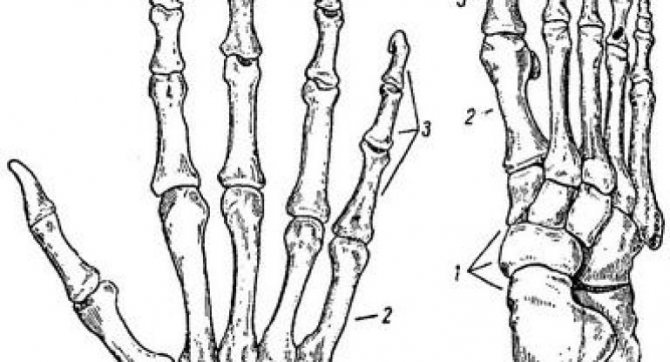

Что представляет собой суставные соединения стопы?

Ступня — это основной рычаг опоры тела человека при перемещении тела в пространстве. Она способна выдерживать огромные нагрузки. Такая функция осуществляется за счет прочности строения связок и суставов, которые работают как целостный механизм амортизации. Плюснефаланговый сустав является составной частью стопы. Это соединение имеет форму шара и значительно укреплено с помощью связок.

Движения в сочленениях плюснефаланговых суставов незначительны, что связано с большим количеством прочных сухожилий, укрепляющих нижнюю конечность.

Из чего состоят пястно-фаланговый и плюснефаланговый суставы: изучаем анатомию

Кисть вместе с пальцами обеспечивает функциональную и трудовую деятельность человека. Руки с помощью мелкой моторики и движения пальцев участвуют в познании окружающего мира и поддержании взаимосвязи с ним. Пястно-фаланговый сустав (ПФС) связывает фаланги каждого из пальцев с неподвижной частью кисти. Немного другую роль выполняют плюснефаланговые суставы ног. Чтобы лучше понять строение сочленений, нужно углубиться в знания анатомии.

Пястно-фаланговые суставы

образованы головками пястных костей и основаниями проксимальных фаланг пальцев. Эти суставы имеют шаровидную форму и три оси вращения. Вокруг этих осей происходят сгибание и разгибание, приведение и отведение, а также круговое движение.

Межфаланговые суставы

имеют блоковидную форму. У них одна фронтальная ось вращения, вокруг которой возможны сгибание и разгибание.